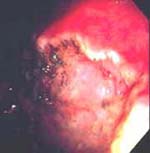

Figura 1. Carcinoma gástrico temprano antral,

pared posterior tipo IIa + IIc.